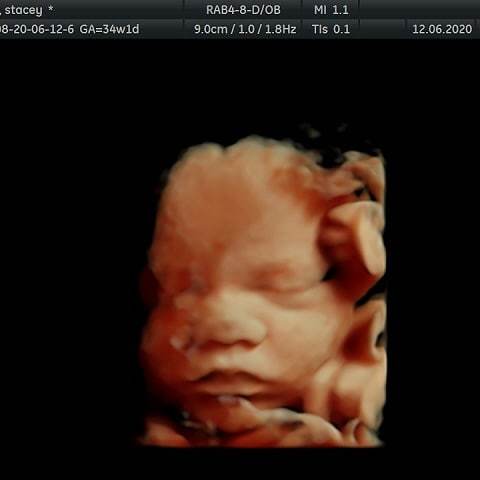

JackGordonsMummy · 12/06/2020 13:22

34 weeks +1 baby Girl has lots of hair and is 5lbs 9oz already 💗🙈

@JackGordonsMummy she looks adorable! Its amazing how clear the 4d pics are. Must make you so much more excited. Did they give you and estimated birth weight if you go full term?? Has she turned down yet?